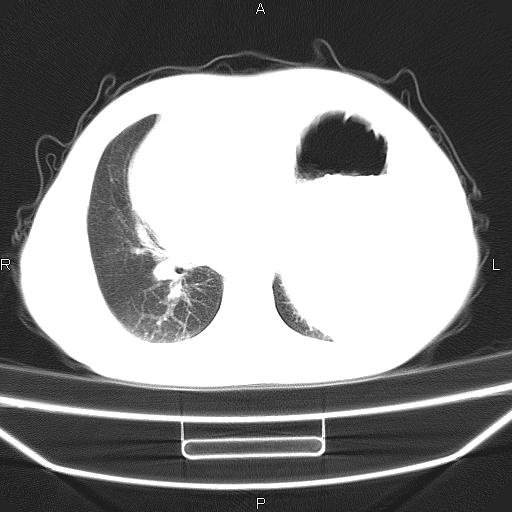

患者,男。50岁。近几日有咳嗽症状,无其他不适,既往病史无,考虑膈疝。请前辈们看看指导指导。

膈膨升,左下肺通气不良,膈肌好像还完整。

考虑左侧膈疝。

左侧膈疝。

符合隔膨升,膈肌较完整。